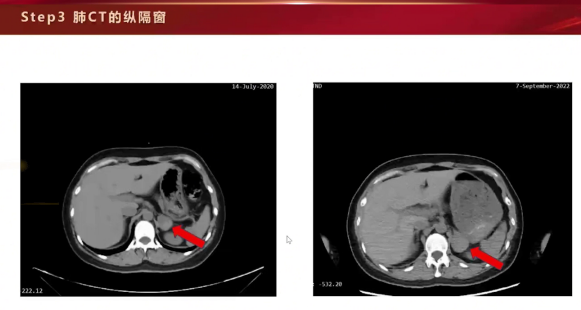

·回顾病史与明确诊断:仔细追问病史,发现症状由体位改变诱发,且与2020年住院症状(头晕、恶心、呕吐、胸闷、血压下降、肺水肿)高度相似。回顾两次CT纵隔窗,发现左侧肾上腺占位,最终诊断为嗜铬细胞瘤及其导致的嗜铬细胞瘤危象(儿茶酚胺危象)、急性儿茶酚胺性心肌病。